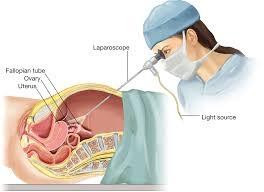

The uterus, ovaries, pelvic peritoneum, and Fallopian tubes may all be operated on during endoscopic reproductive surgery to promote fertility. Hysteroscopy and laparoscopy are included. Hysteroscopy is a telescopic examination of the uterine cavity from the inside to diagnose and correct cavity abnormalities that interfere with normal fertility. Laparoscopy is a minimally invasive surgical method that enables for surgery at the time of diagnosis by providing a panoramic and magnified image of the pelvic organs.

Office hysteroscopy is a type of diagnostic hysteroscopy that is conducted in an out-patient department as an OPD based technique that does not require anaesthesia. Hysteroscopes with a diameter of 2.9mm or 2mm are required. Surgical techniques such as polypectomy and adhesiolysis can be performed using office hysteroscopy.